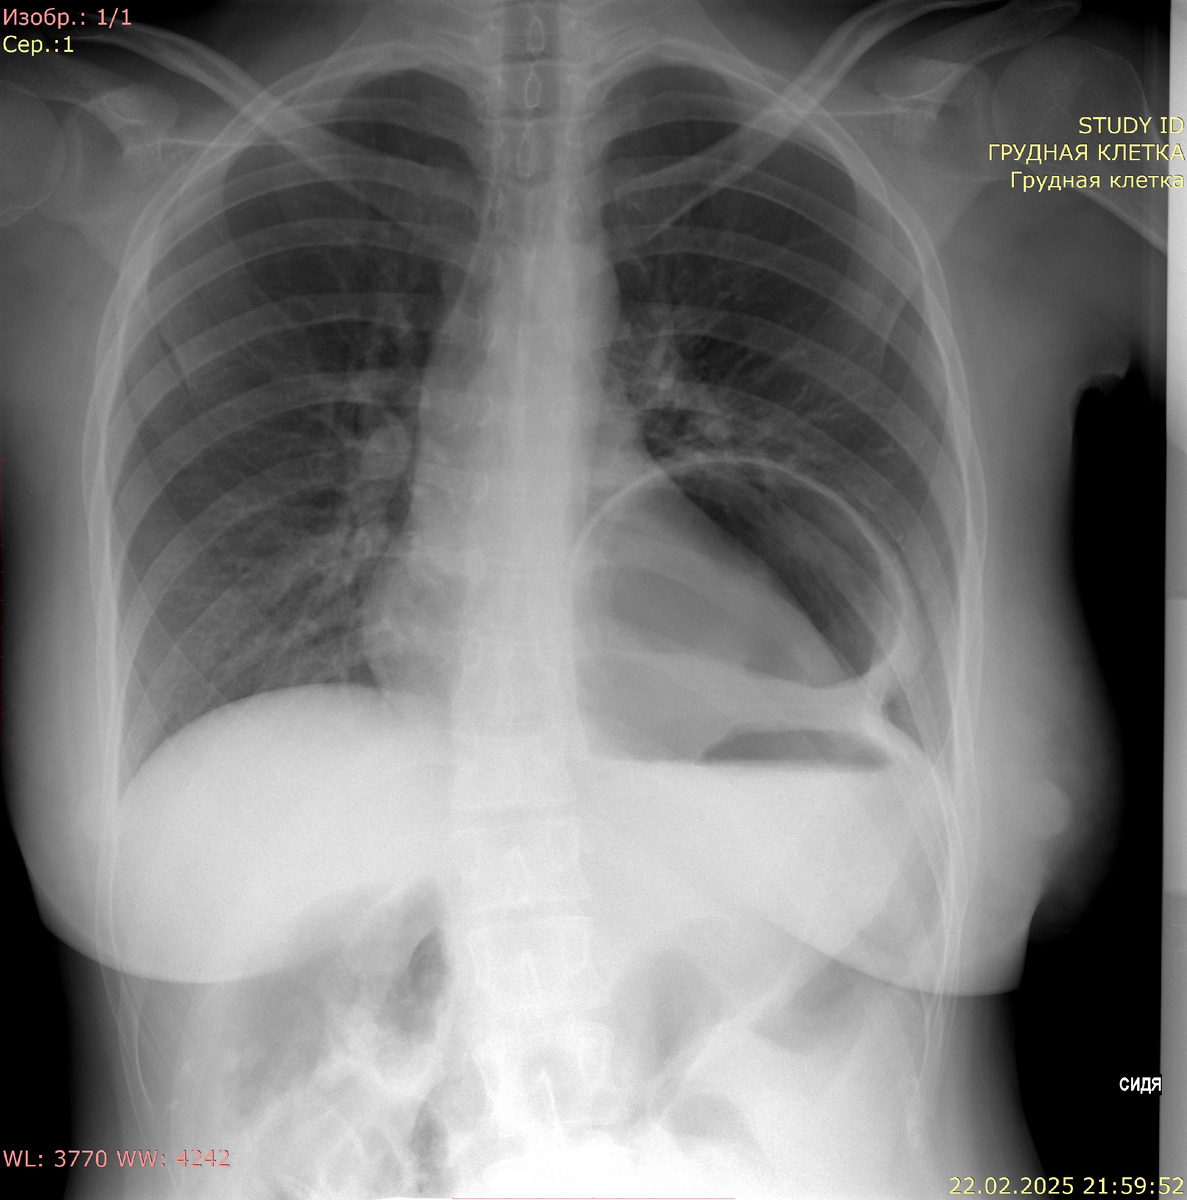

Рентгенография органов брюшной полости в прямой проекции:

В проекции грудной полости слева под куполом диафрагмы визуализируется желудок с уровнем "жидкость-газ", диаметр 10 см. Под куполами диафрагмы свободный газ не определяется.

Заключение: данных за свободный газ не получено. Картина может соответствовать диафрагмальной грыже (содержимое - желудок).